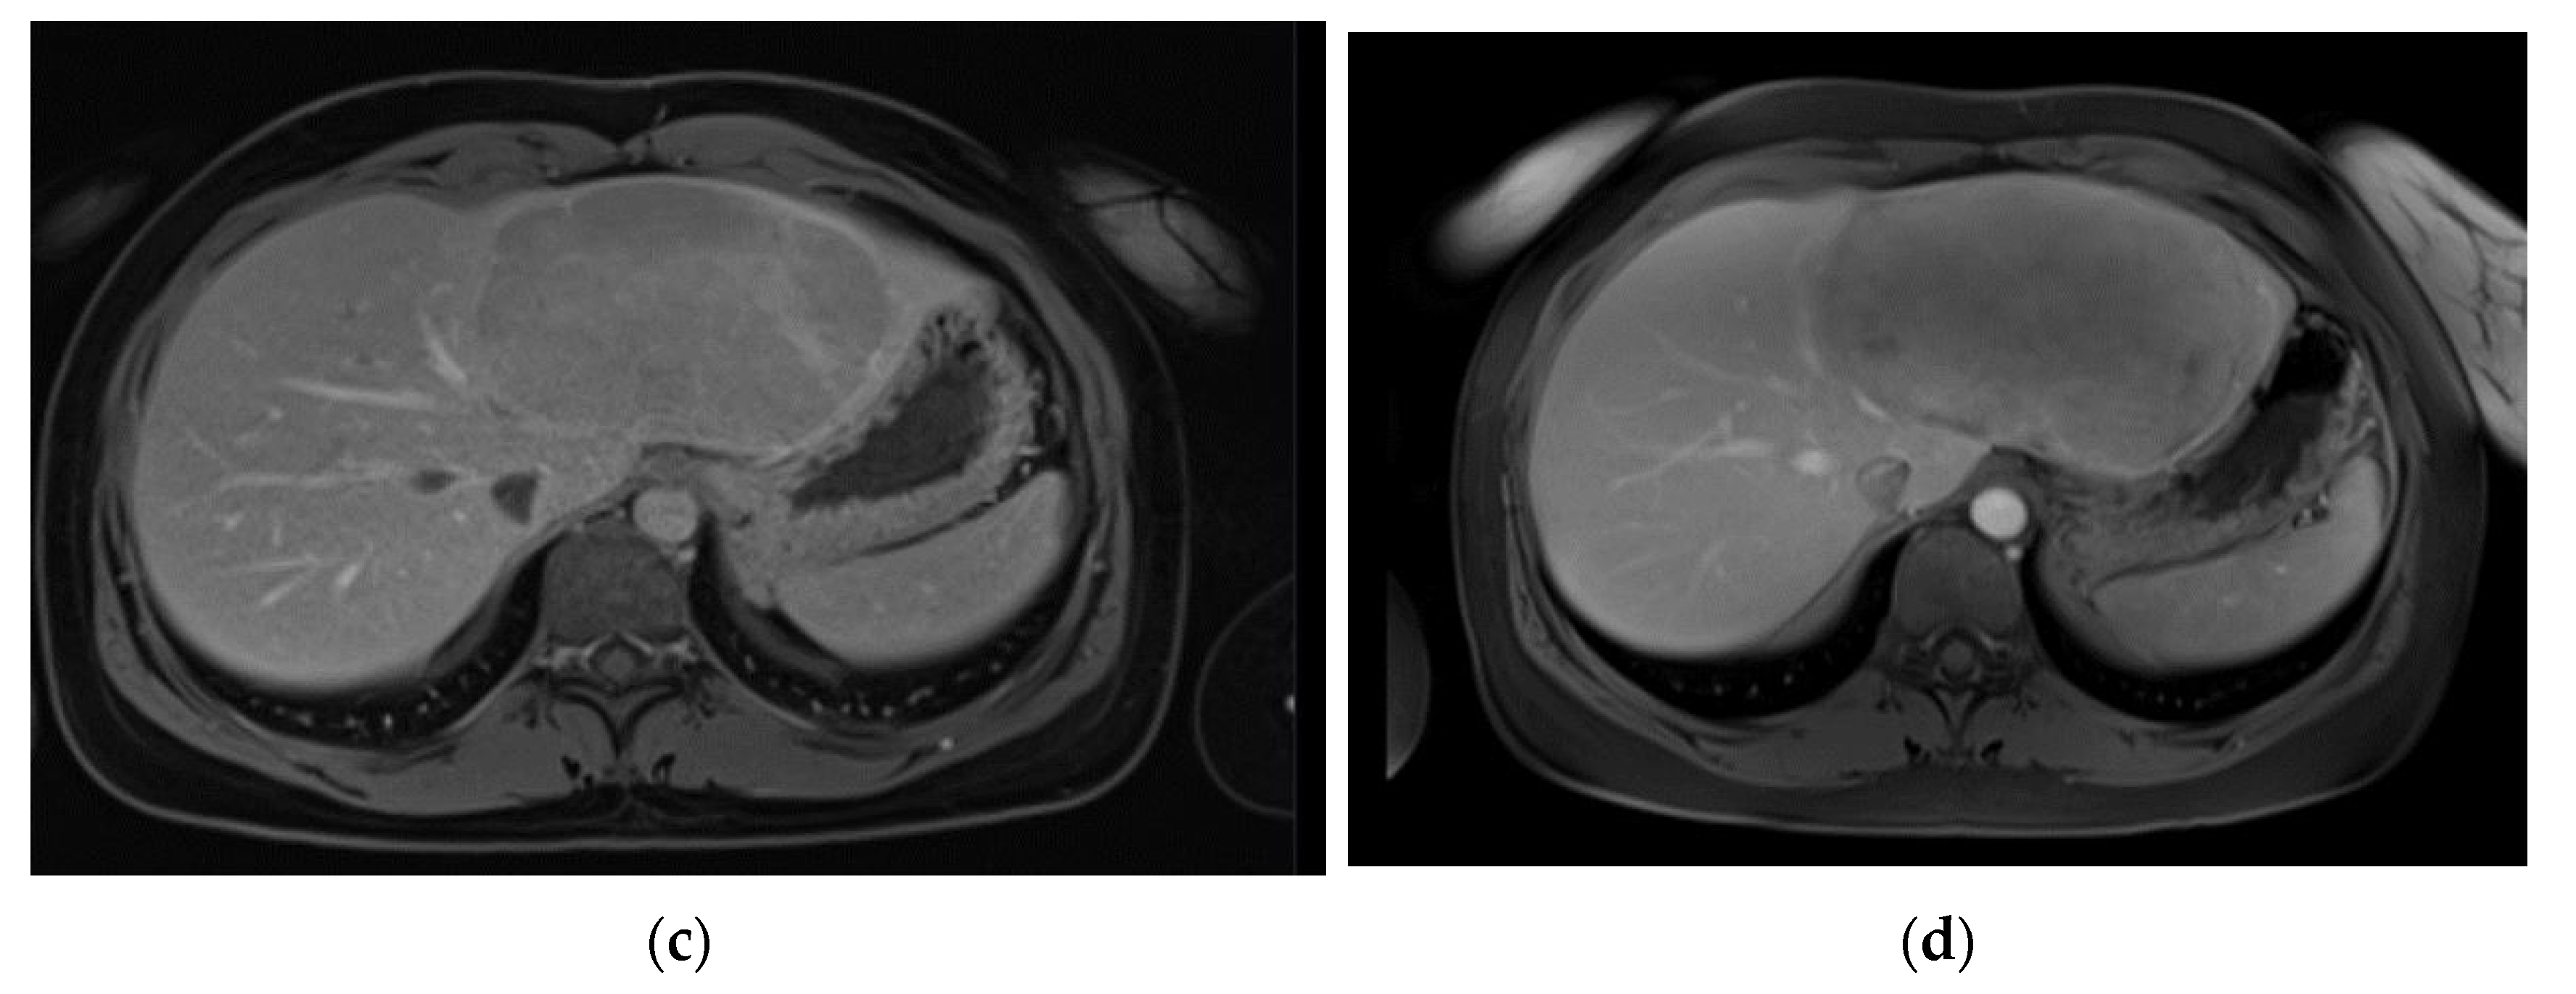

Figure 3. Pre-operative MR imaging Patient 3: (a) T2 TSE sequence depicting central scar; (b) T1 sequence with fat saturation in depicting intense early arterial enhancement; (c) Late venous phase imaging showing iso-/hyperintensity of solid components to healthy liver tissue.

The third patient was 53 years old when a FNH was diagnosed in MRI (Figure 3). Comparable to patient 1, no dedicated delayed hepatobiliary phase had been was performed. A follow-up after 3 months was scheduled, this time with Alpha-1 Fetoprotein (AFP) as laboratory testing, which turned out to be significantly increased with a value of > 400000ng/ml. At presentation at our center four weeks later the AFP had risen to 980,128 ng/ml. We conducted a central resection of segments 4, partially 5 and 8 as well as Segment 1 (H145′8′-RHV). Resection and reconstruction of the right hepatic vein was necessary to achieve R0-status. The patient is tumor-free within follow-up for 20 months until today. In the postoperative course the AFP levels decreased to 5529 ng/ml after one month, to 4.9 ng/ml after three months, and remained below 2.5 ng/ml since seven months after resection.